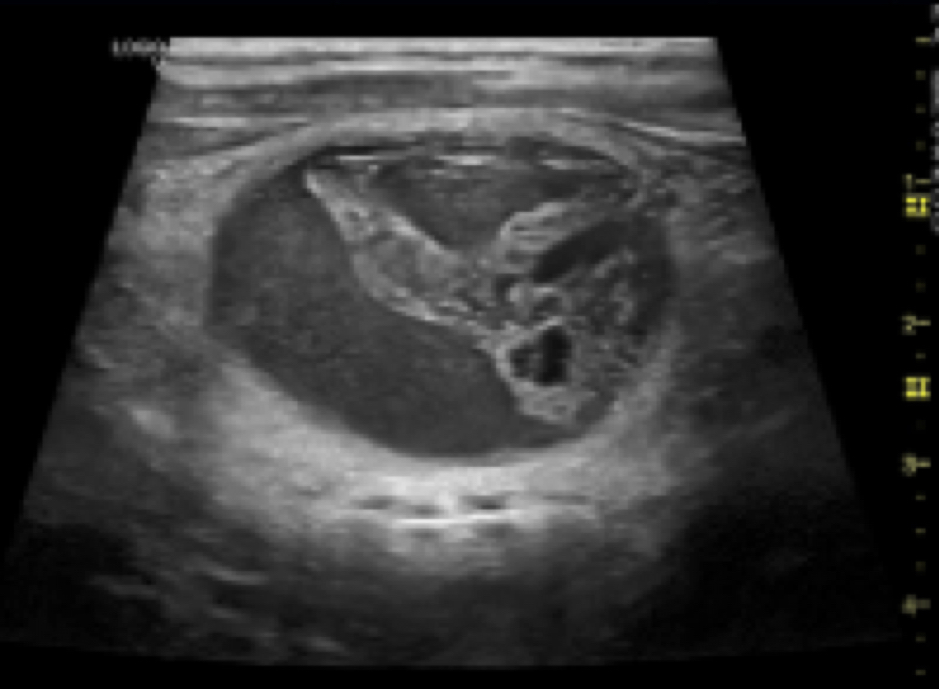

-SONDA CONVEX 4C – RS

Sonda Convexa, múltifrecuencia (1,4 a 4,8 MHz) y de gran ancho de banda, de utilización en aplicaciones de Ecografía General. Radio de 60mm y 55º de ángulo de visión. Disponible como opción la guía de biopsia.